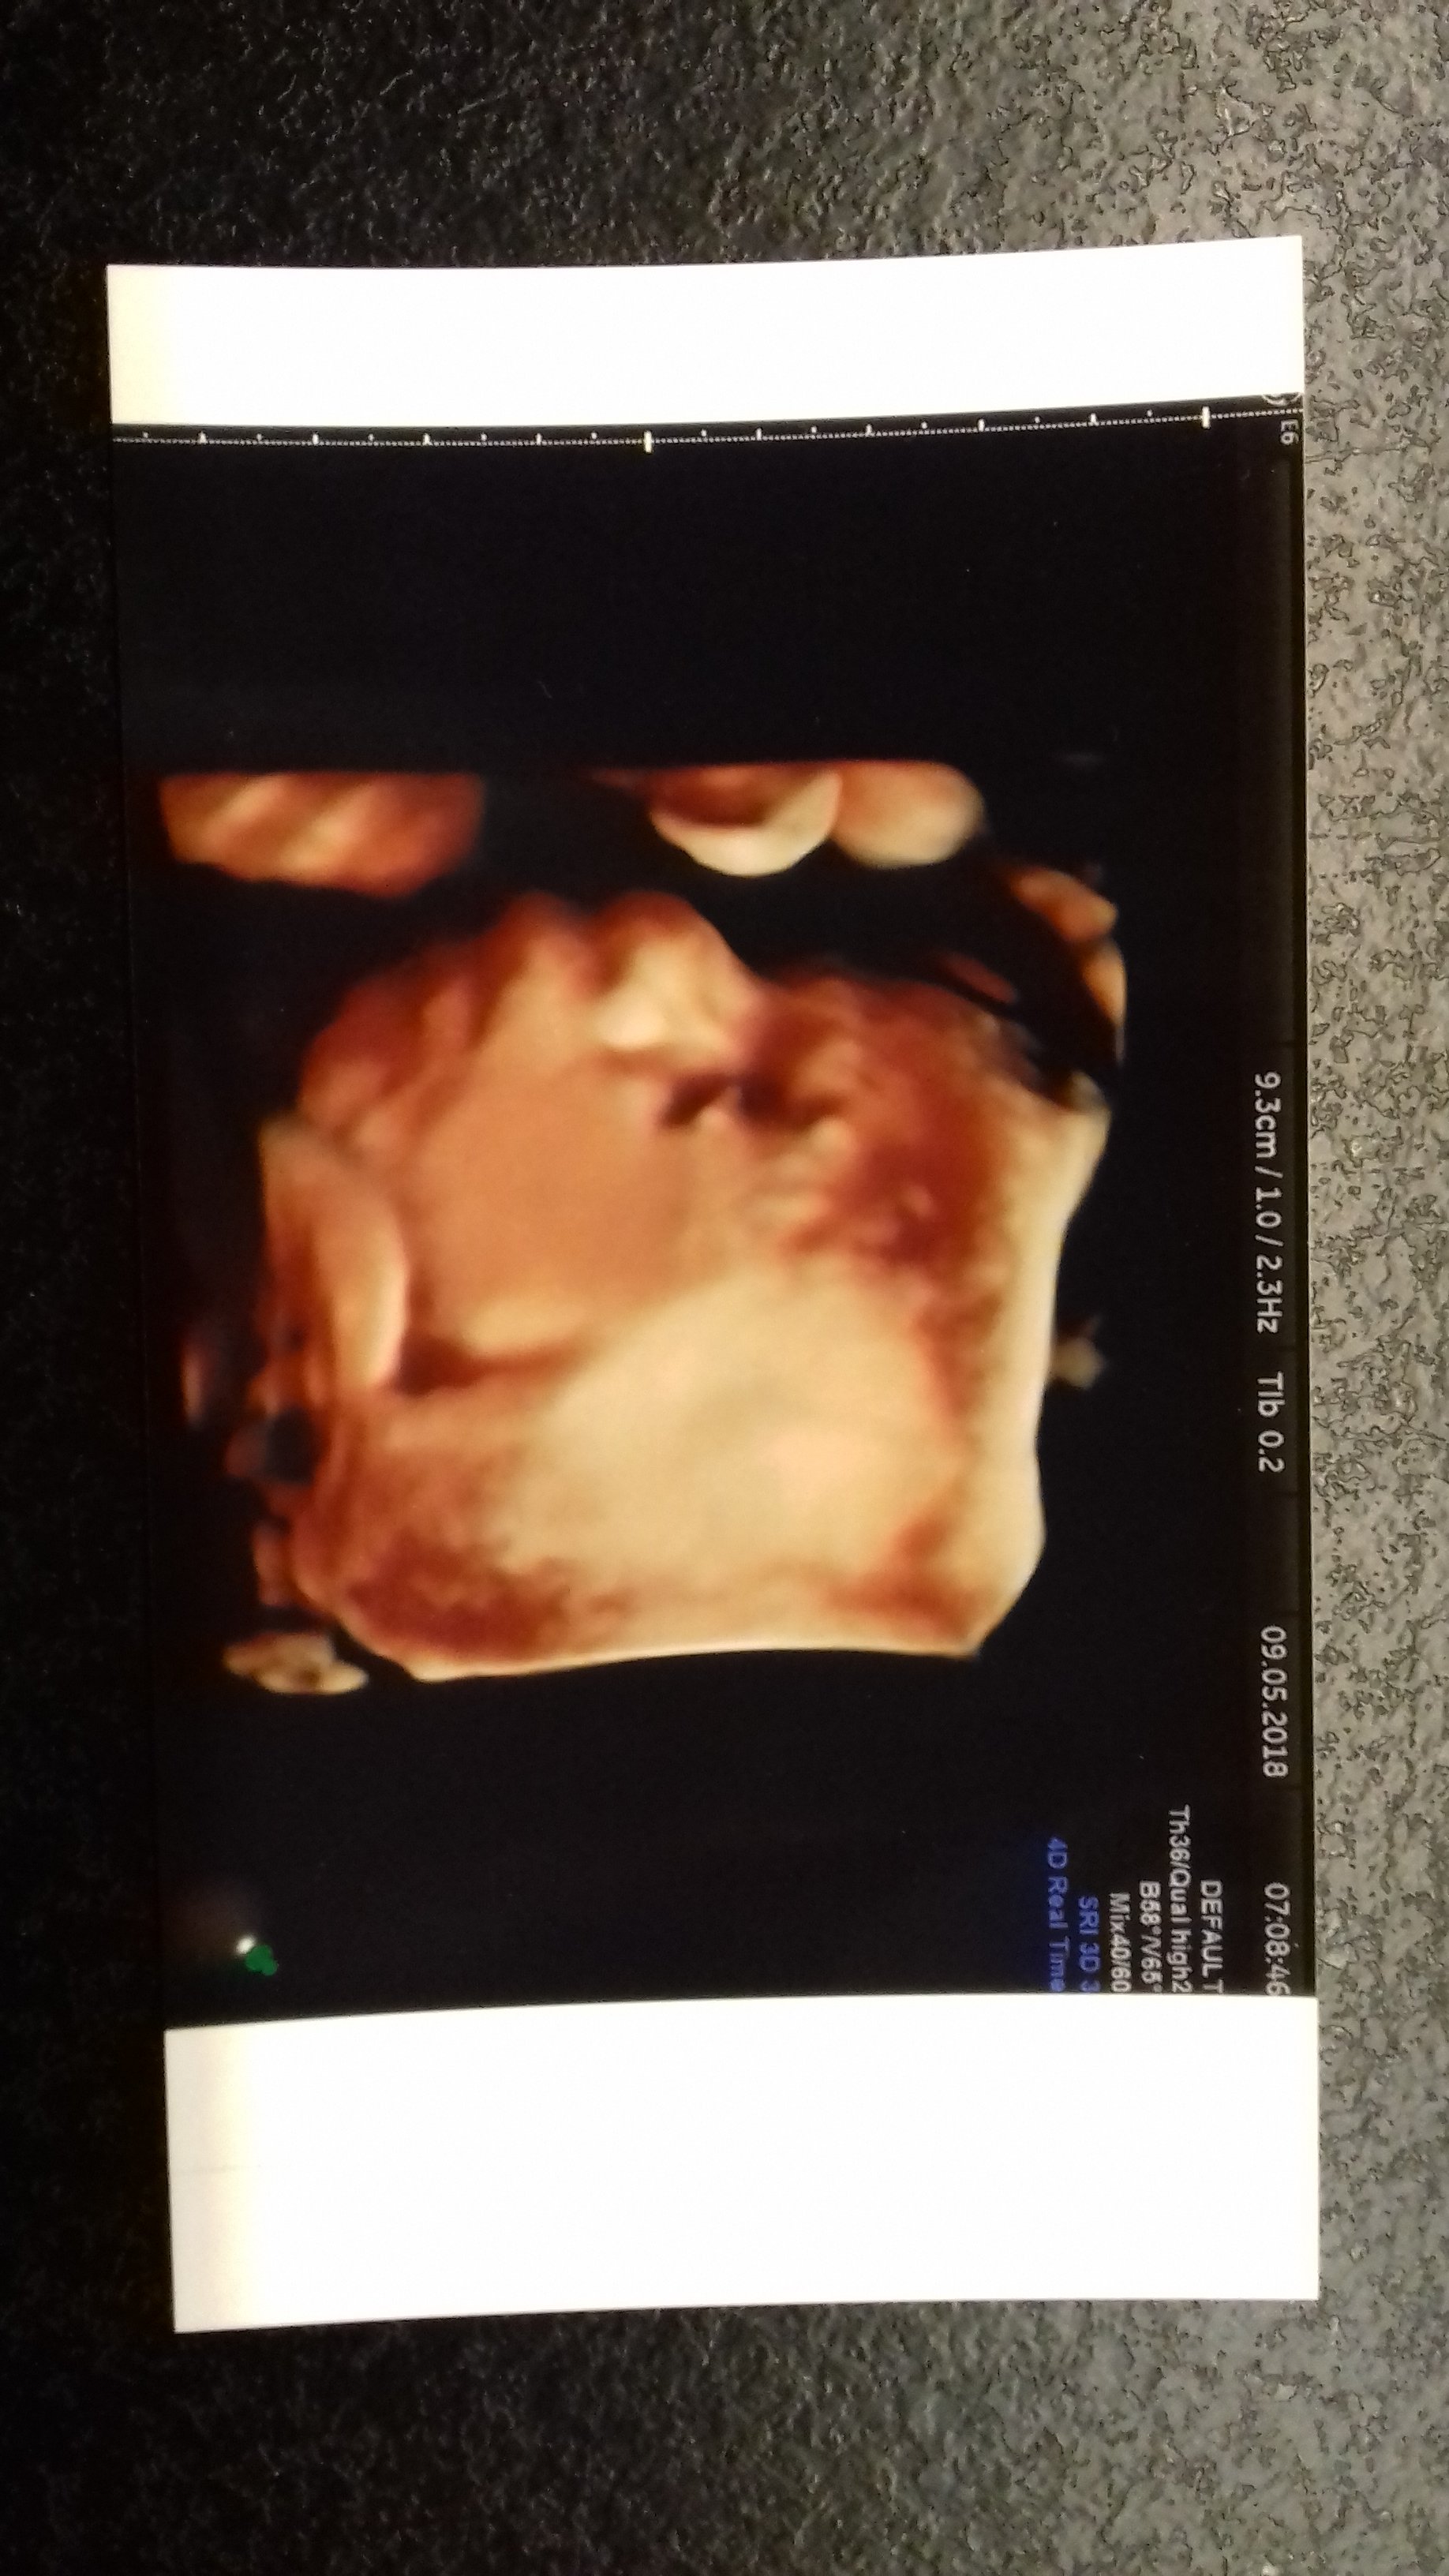

Jeju, tak piszecie o tym waszym młodszym rodzeństwie w wieku dwudziestu paru lat i masakra. Ja tez co prawda jestem młoda, bo rocznik 95, więc koncze za miesiąc 23 lata. Ale całkowicie się różnie od tego schematu, który piszecie. Wiadomo, dziewczyny inaczej i szybciej dojrzewają, ale i tak czuje się dojrzalsza niż osoby w moim wieku. Tu nie chodzi o ciążę, jasne - ona dużo tez zmieniła w mojej głowie i to na dobre, ogarnelam się, spokojniejsza się zrobiłam, mam inne ważniejsze priorytety w życiu niż wcześniej, ale nadal nie stałam się tez stara maleńka